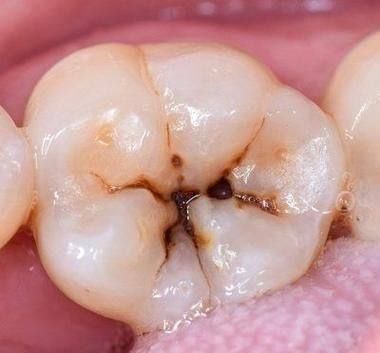

龋洞大小与深度的影响

龋洞的大小和深度是判断是否需要填补的重要因素。如果龋洞比较小而且浅,这时候不用过于着急补牙。我们可以通过改善口腔卫生习惯,比如认真刷牙、使用牙线等,再配合使用含氟牙膏或者氟化物漱口水,促进牙齿的再矿化。牙齿自身有一定的修复能力,在良好的口腔环境下,小而浅的龋洞有可能慢慢修复。

然而,如果龋洞较大或者较深,那就不能掉以轻心了。大而深的龋洞会影响牙齿的结构和功能,牙齿可能会变得脆弱,容易折断。而且,食物残渣更容易残留在龋洞里,滋生细菌,导致龋齿继续发展。所以,这种情况下应该及时填补龋洞,防止龋齿进一步恶化。